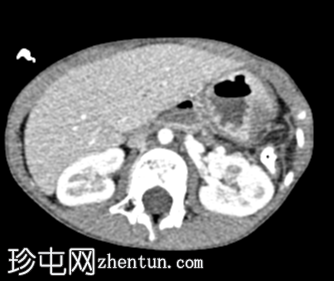

轴向C+期

动脉期

左侧膈疝通过位于左膈中部的一个缺损形成,伴有纵隔向右侧移位,下方左塌陷。

脾脏、大肠和小肠均有疝气,同时伴有肠系膜上血管疝气。

胃位于下部,靠近主动脉分叉处。